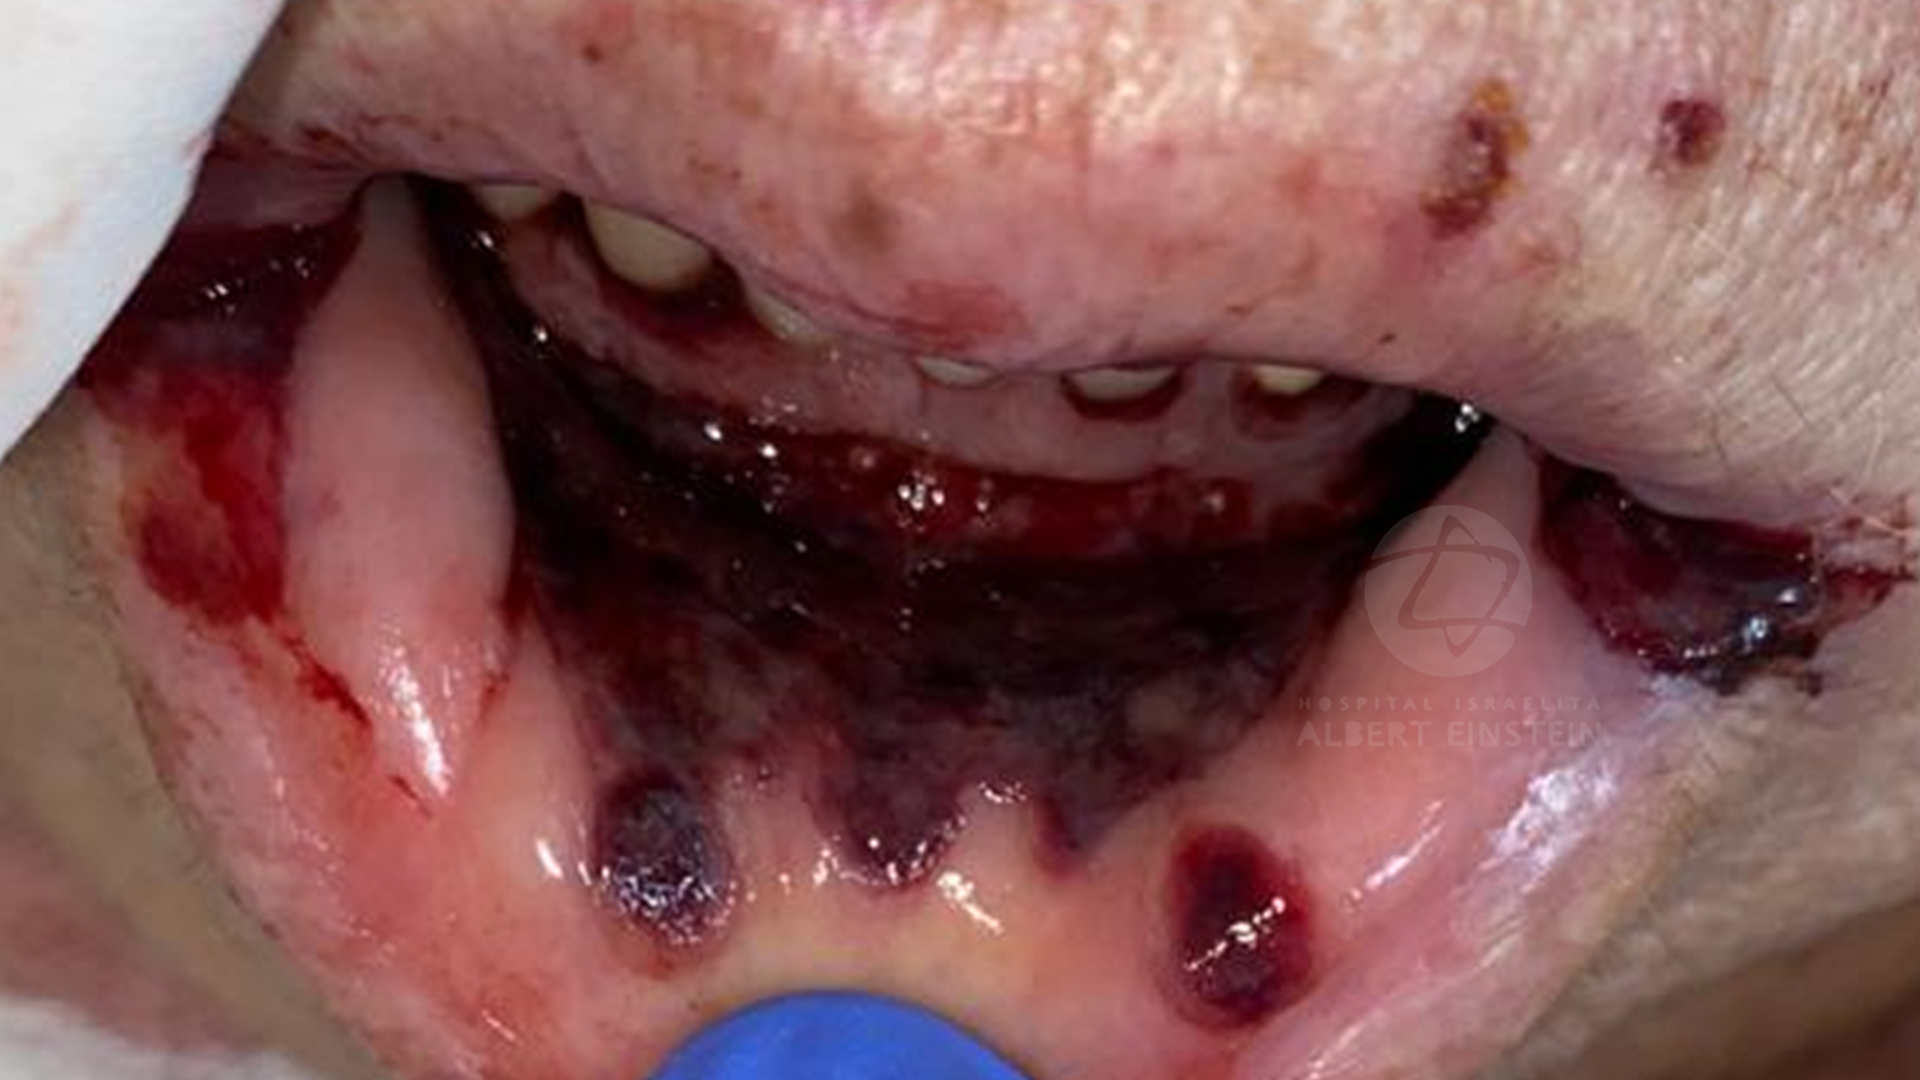

In this presentation, we will show our protocol for oral management of COVID-19 patients, emphasizing the importance of oral lesions diagnosis and treatment. We will discuss if the oral lesions can be derived from the direct virus action on the oral mucosa or derived from the systemic condition of the patient. All the clinical cases will have a background of the scientific literature about the clinical significance of SARS-CoV-2 in the oral cavity

- The most frequent oral lesions presented in COVID-19 patients.

- How to diagnosis and treat these lesions.

- The clinical significance of the possible SARS-CoV-2 action in the oral cavity.